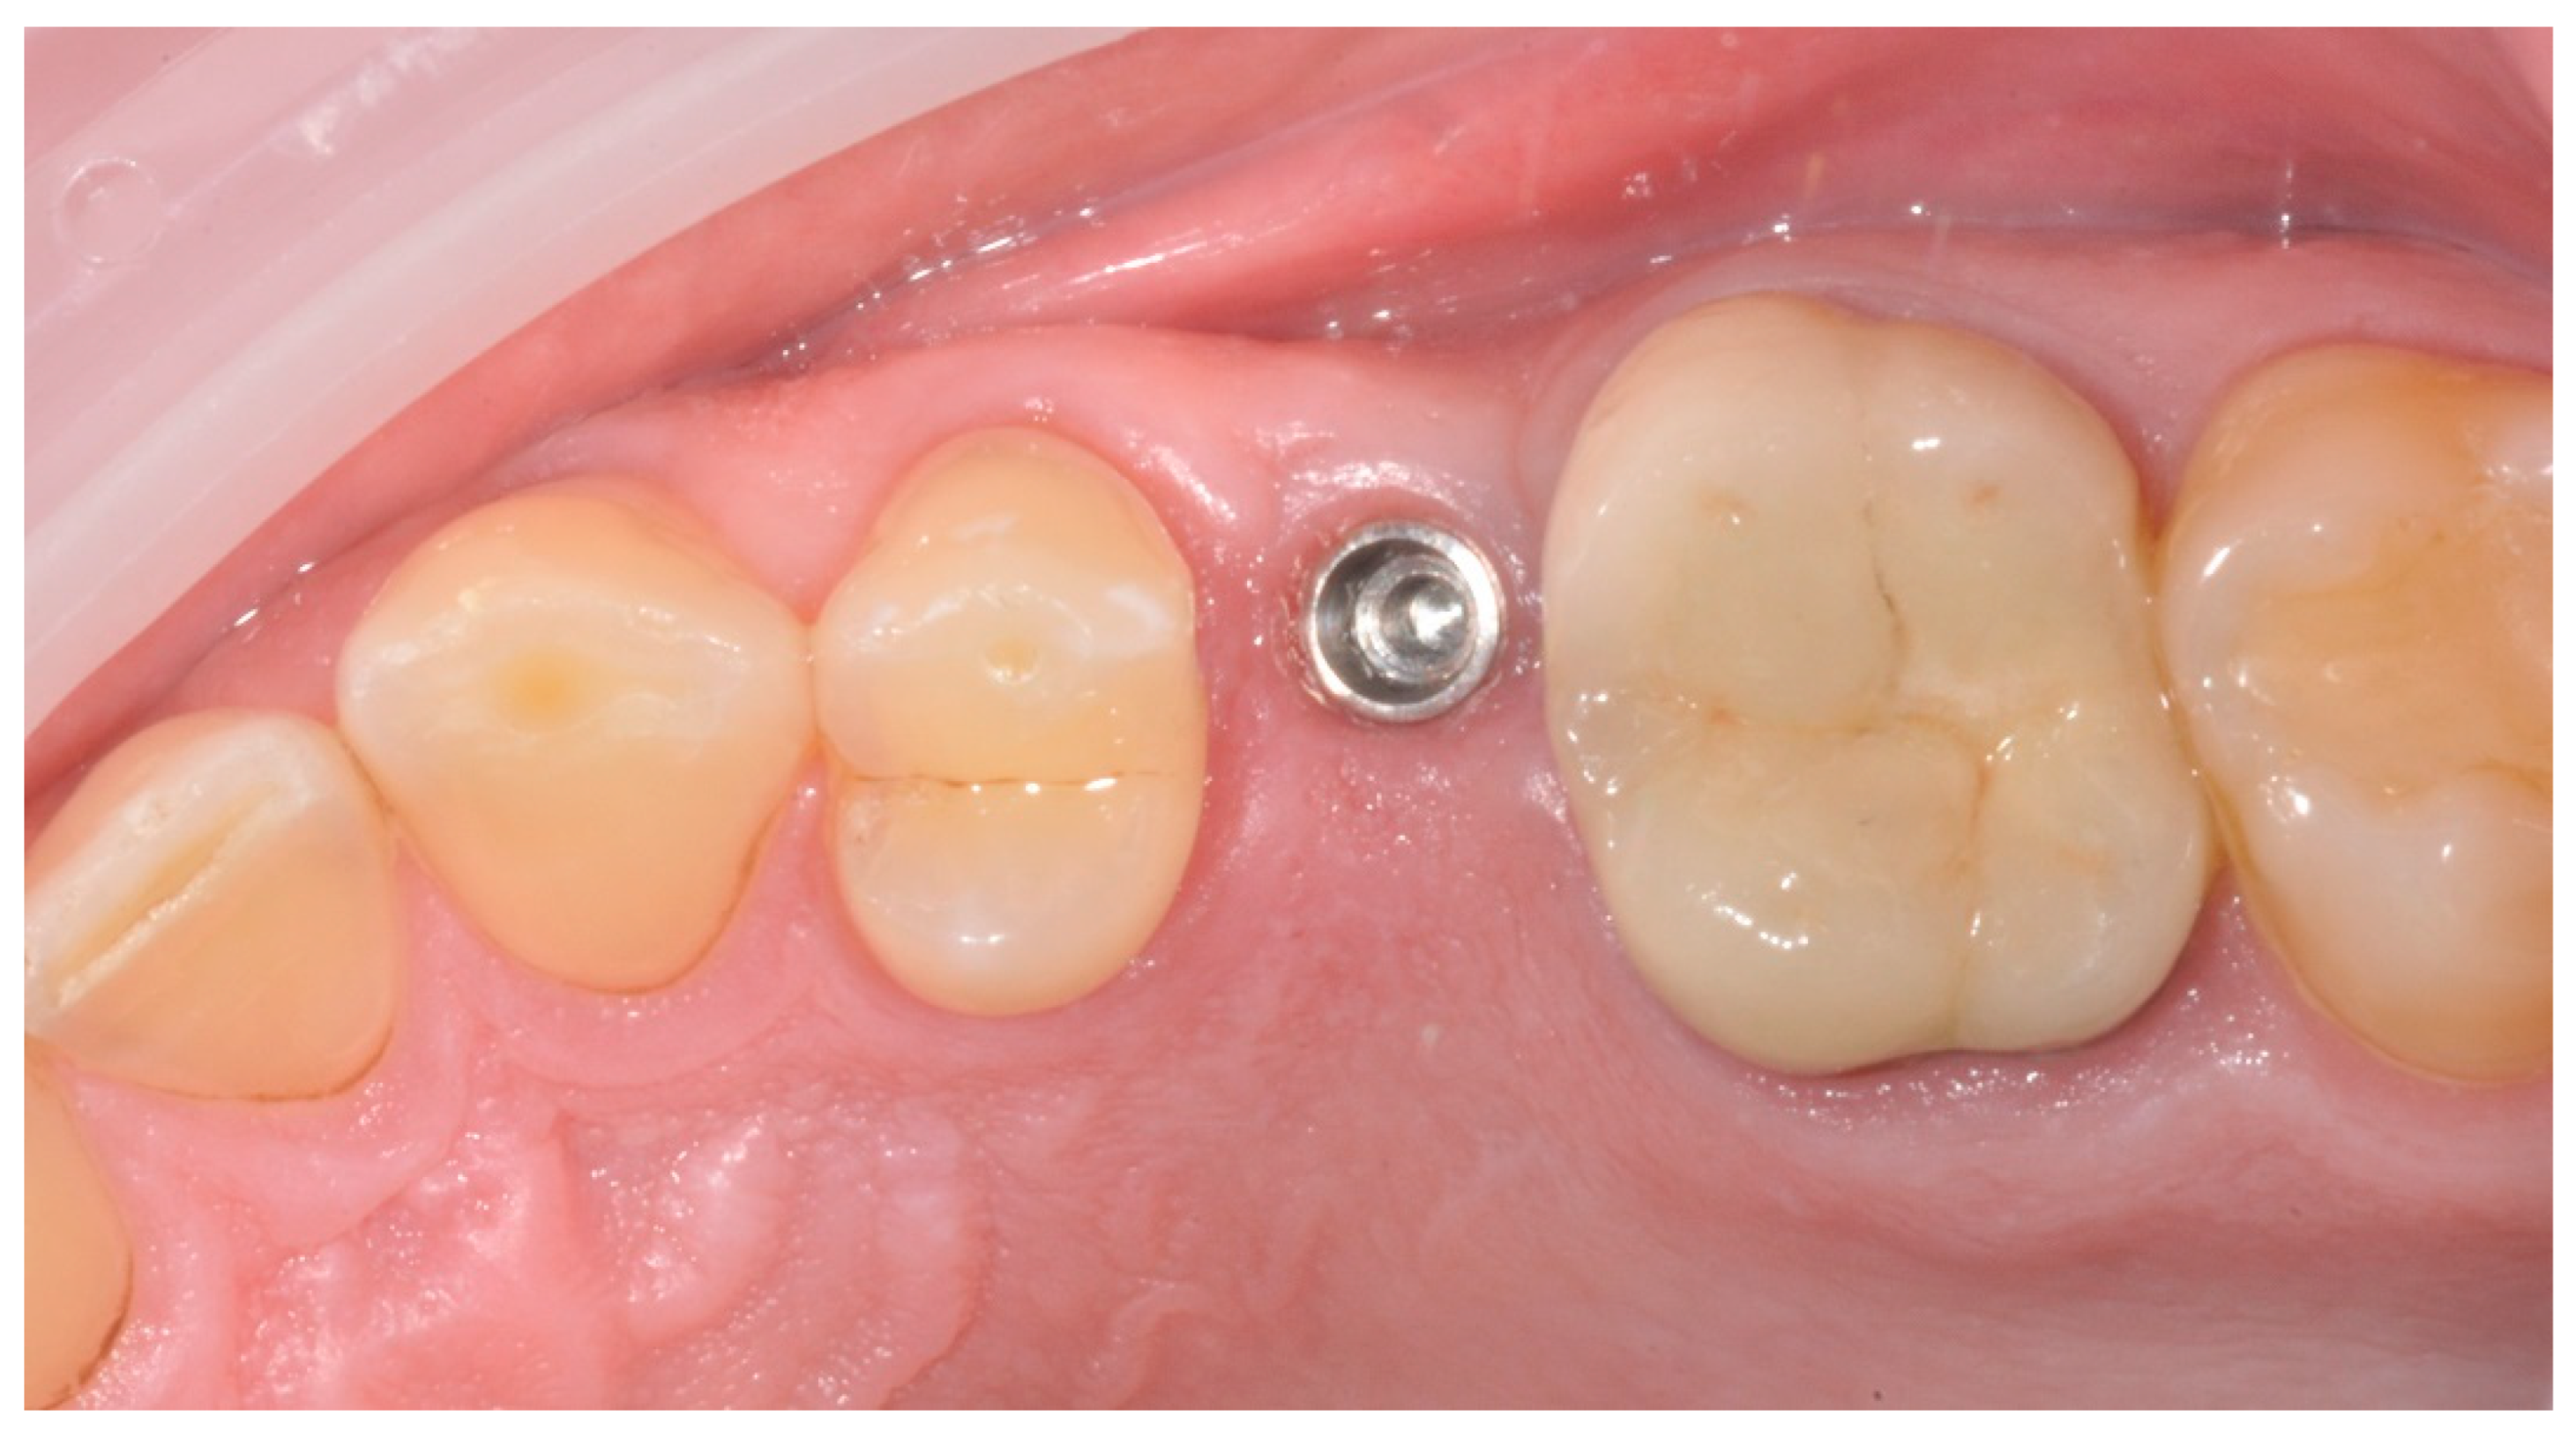

2.2. Surgical Procedures

2.3. Prosthetic Protocol